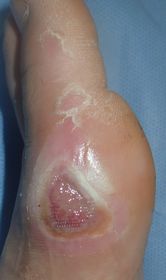

7歳男。

受賞後,しばらく歩こうとせずに松葉杖で歩いていたが,11月10日,突然走りだした。

| 10月27日 | 10月29日 | 11月6日:10日後 | 11月13日:17日後 |